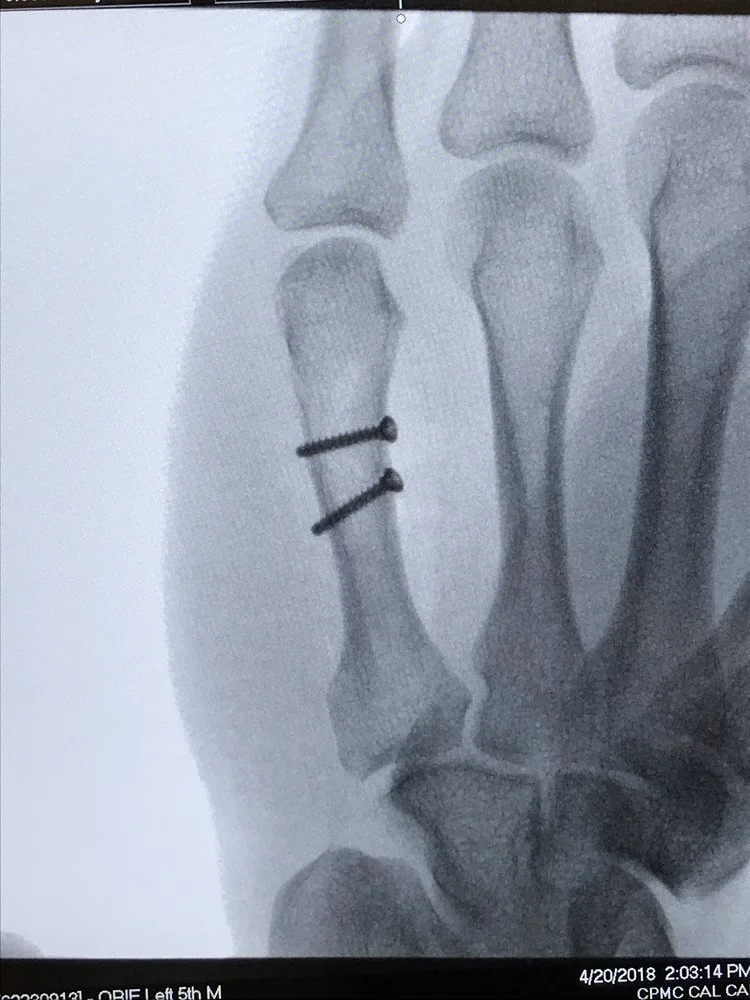

Metacarpal Fracture